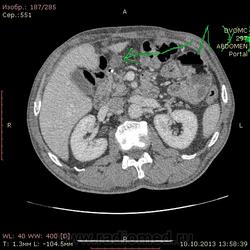

69 лет. КТ контроль от августа. Посте очередного курса химии. Начало истории здесь http://www.radiomed.ru/cases/kt-bryushnoi-polosti-adenokartsinoma-zheludka-sostoyanie-posle-rezektsii-zheludka-mts-v-pechen

Сегодня выглядит так. DICOM здесь http://files.mail.ru/2A18DCE6A6AA4546B51713D2F9C9E91A

На мой взгляд метастазов новых нет, но старые увеличились и один из пораженных л\у также увеличился.